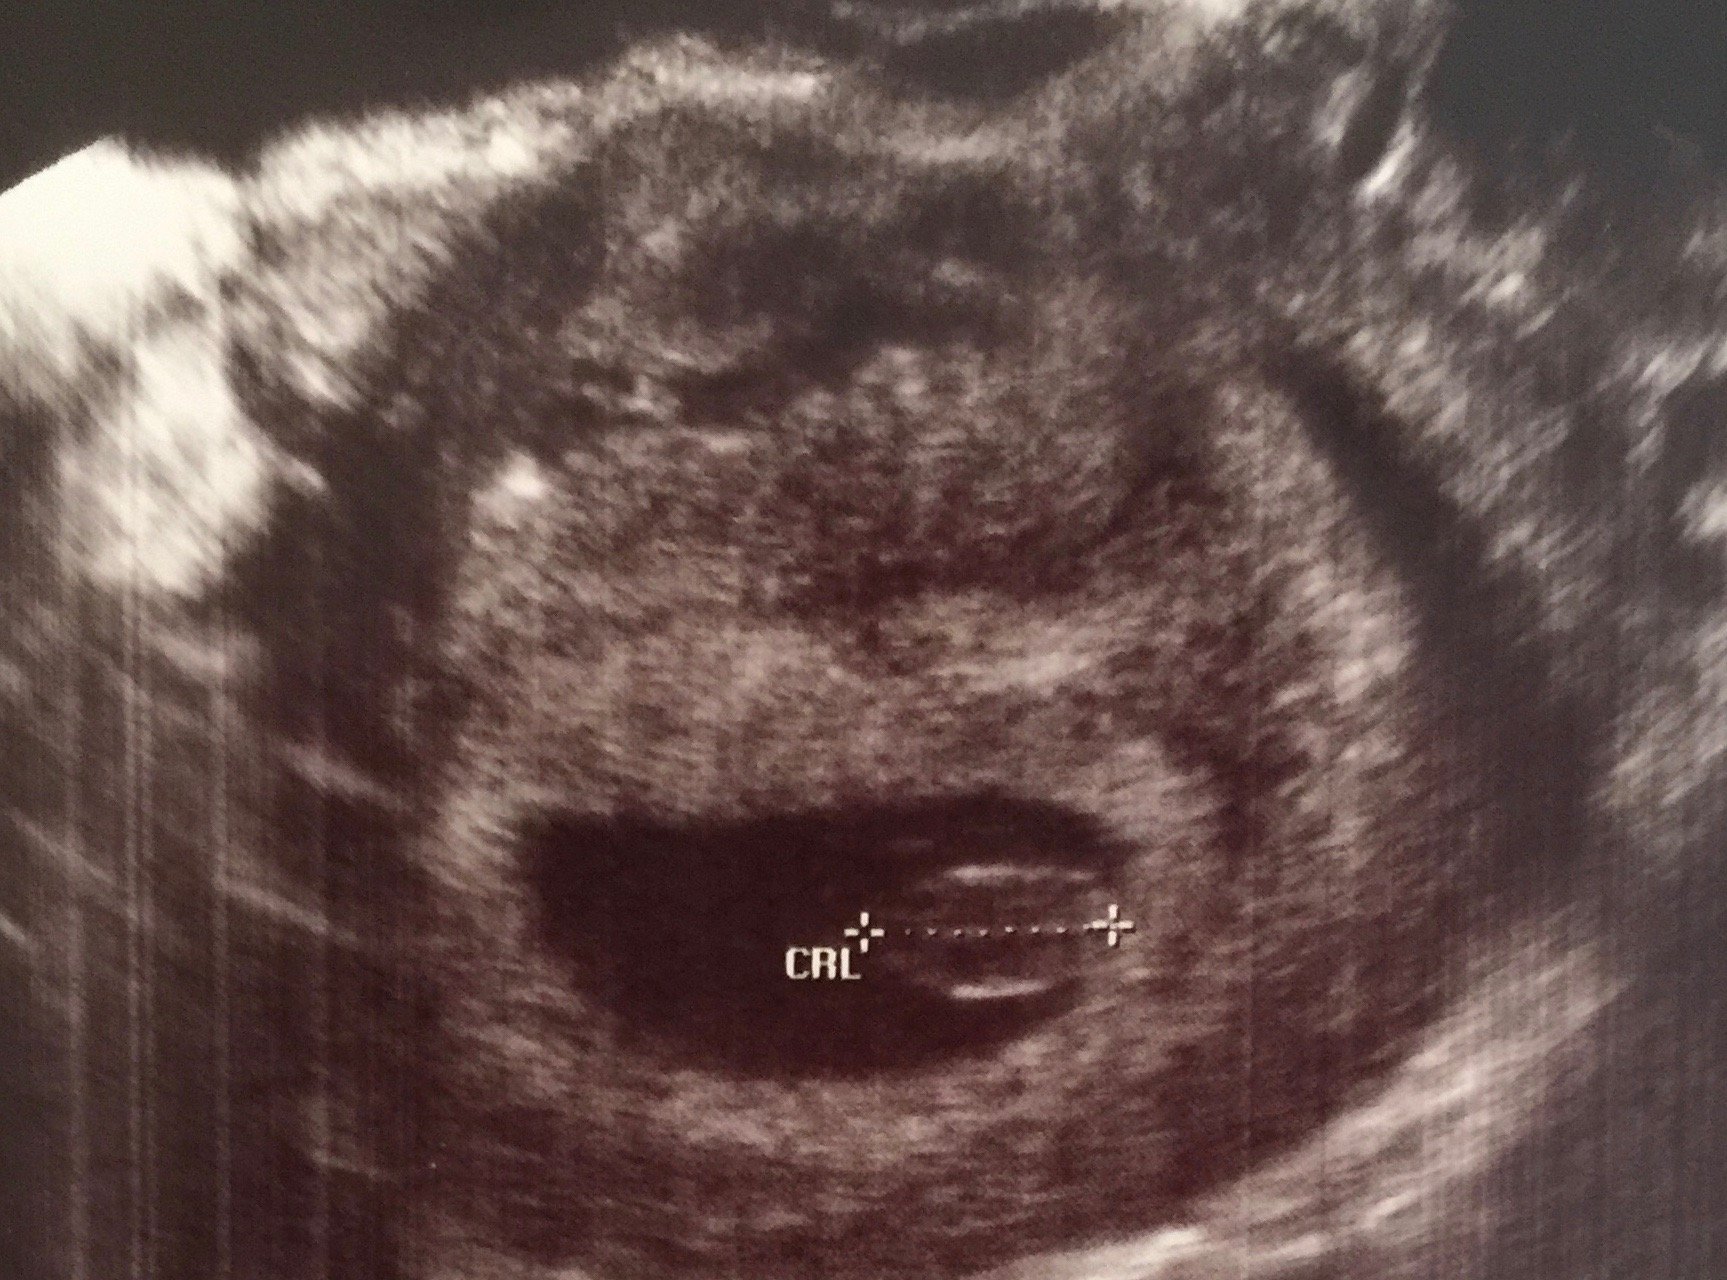

FINALLY!!!! Got to see our little jelly bean! Measuring 7 weeks on the dot and heart rate was strong 137!! So in love and it definitely has made reality set in!